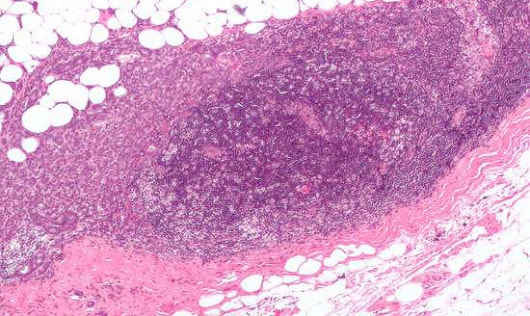

リンパ液の中にはリンパ球があり、リンパ管に集まってきます。リンパ管は、血管と同じように全身にはりめぐらされていますが、ところどころに関所のような役目をするところがありますそれがリンパ節(リンパ腺)で、免疫にかかわる細胞(リンパ球など)があって、リンパに入ってきた細菌などの働きを弱めたり死滅させたりします。

細菌やウイルスに感染すると、こういった免疫系の仕組みが働いてリンパ節が腫れますが、さわると痛みがあります。また、がんの転移でもリンパ節が腫れますが、痛みはなく、ごつごつと硬いのが特徴です膠原病の腫れとの違いとして、参考にしてください。